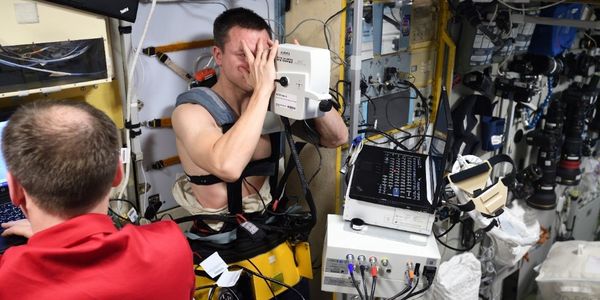

How can long-term space flight influence astronaut health, and specifically their organs? This is what a recent study published in Nature Communications ho